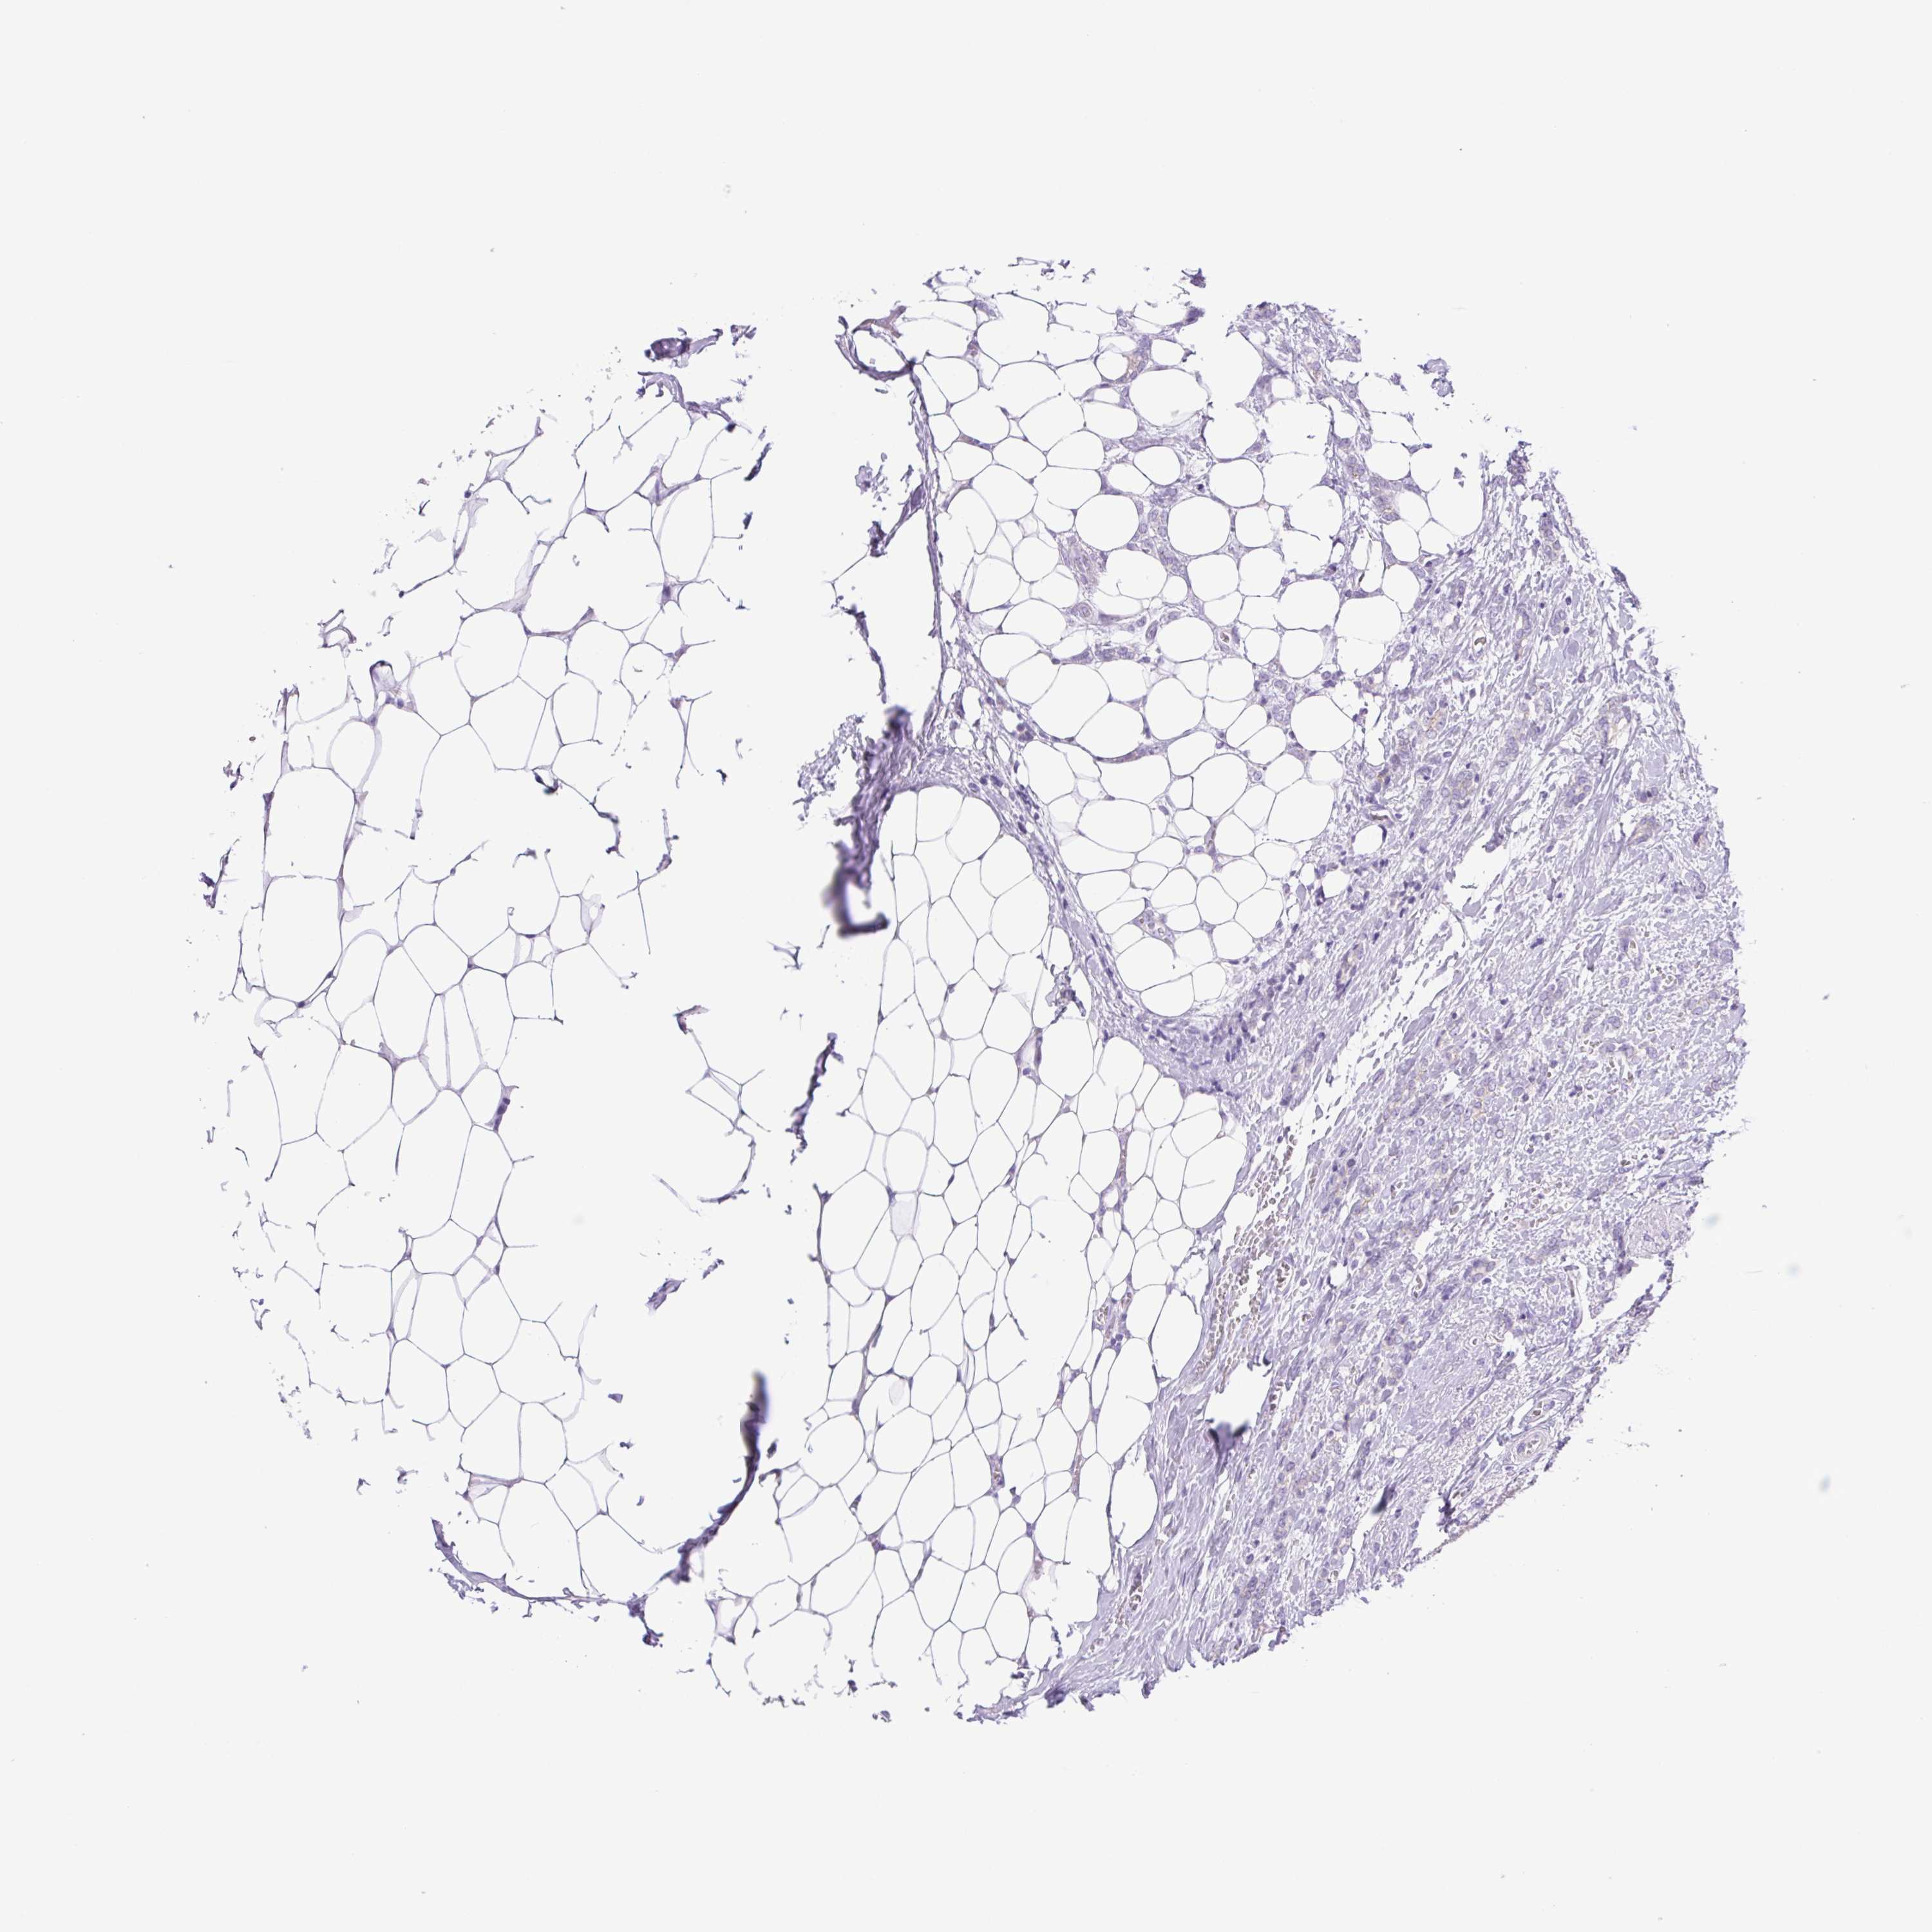

CANCER BREAST CANCER Show tissue menu

BRCA TCGA BRCA VALIDATION PROTEIN EXPRESSION

Breast cancer

Human cancer

Breast invasive carcinoma